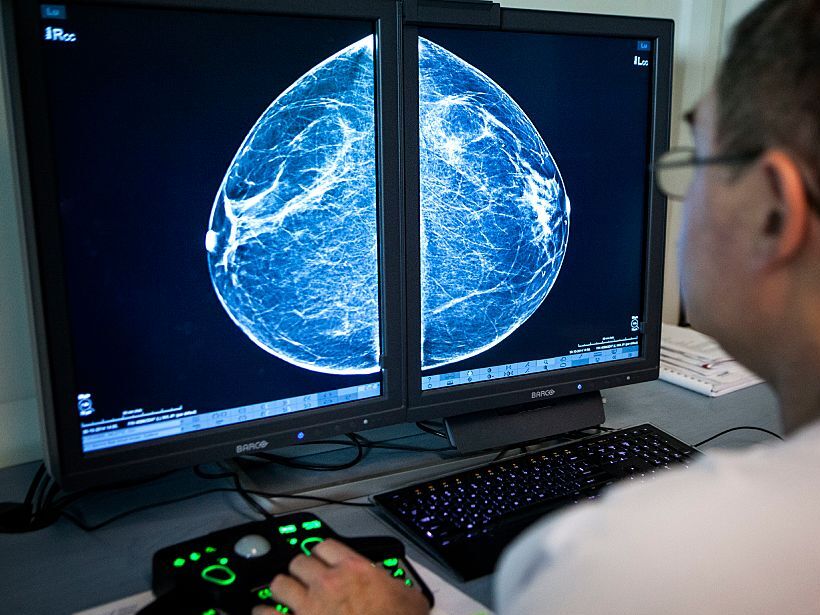

caption: When radiologists review mammograms for signs of breast cancer, they can also see arterial calcification in the breast, which is linked with cardiovascular disease risk.

When radiologists review mammograms for signs of breast cancer, they can also see arterial calcification in the breast, which is linked with cardiovascular disease risk.

Although breast X-rays are typically used to detect and diagnose breast cancer, the pictures also indicate whether the arteries in the breast have calcifications, which show up as parallel white lines on the film. Calcifications, which are considered “incidental” findings unrelated to breast cancer, may be associated with someone’s heart disease risk.